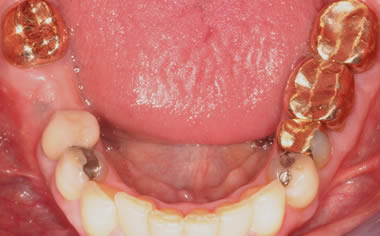

More back teeth replaced by dental implants

Case Four (4 images)

Case Five (4 images)